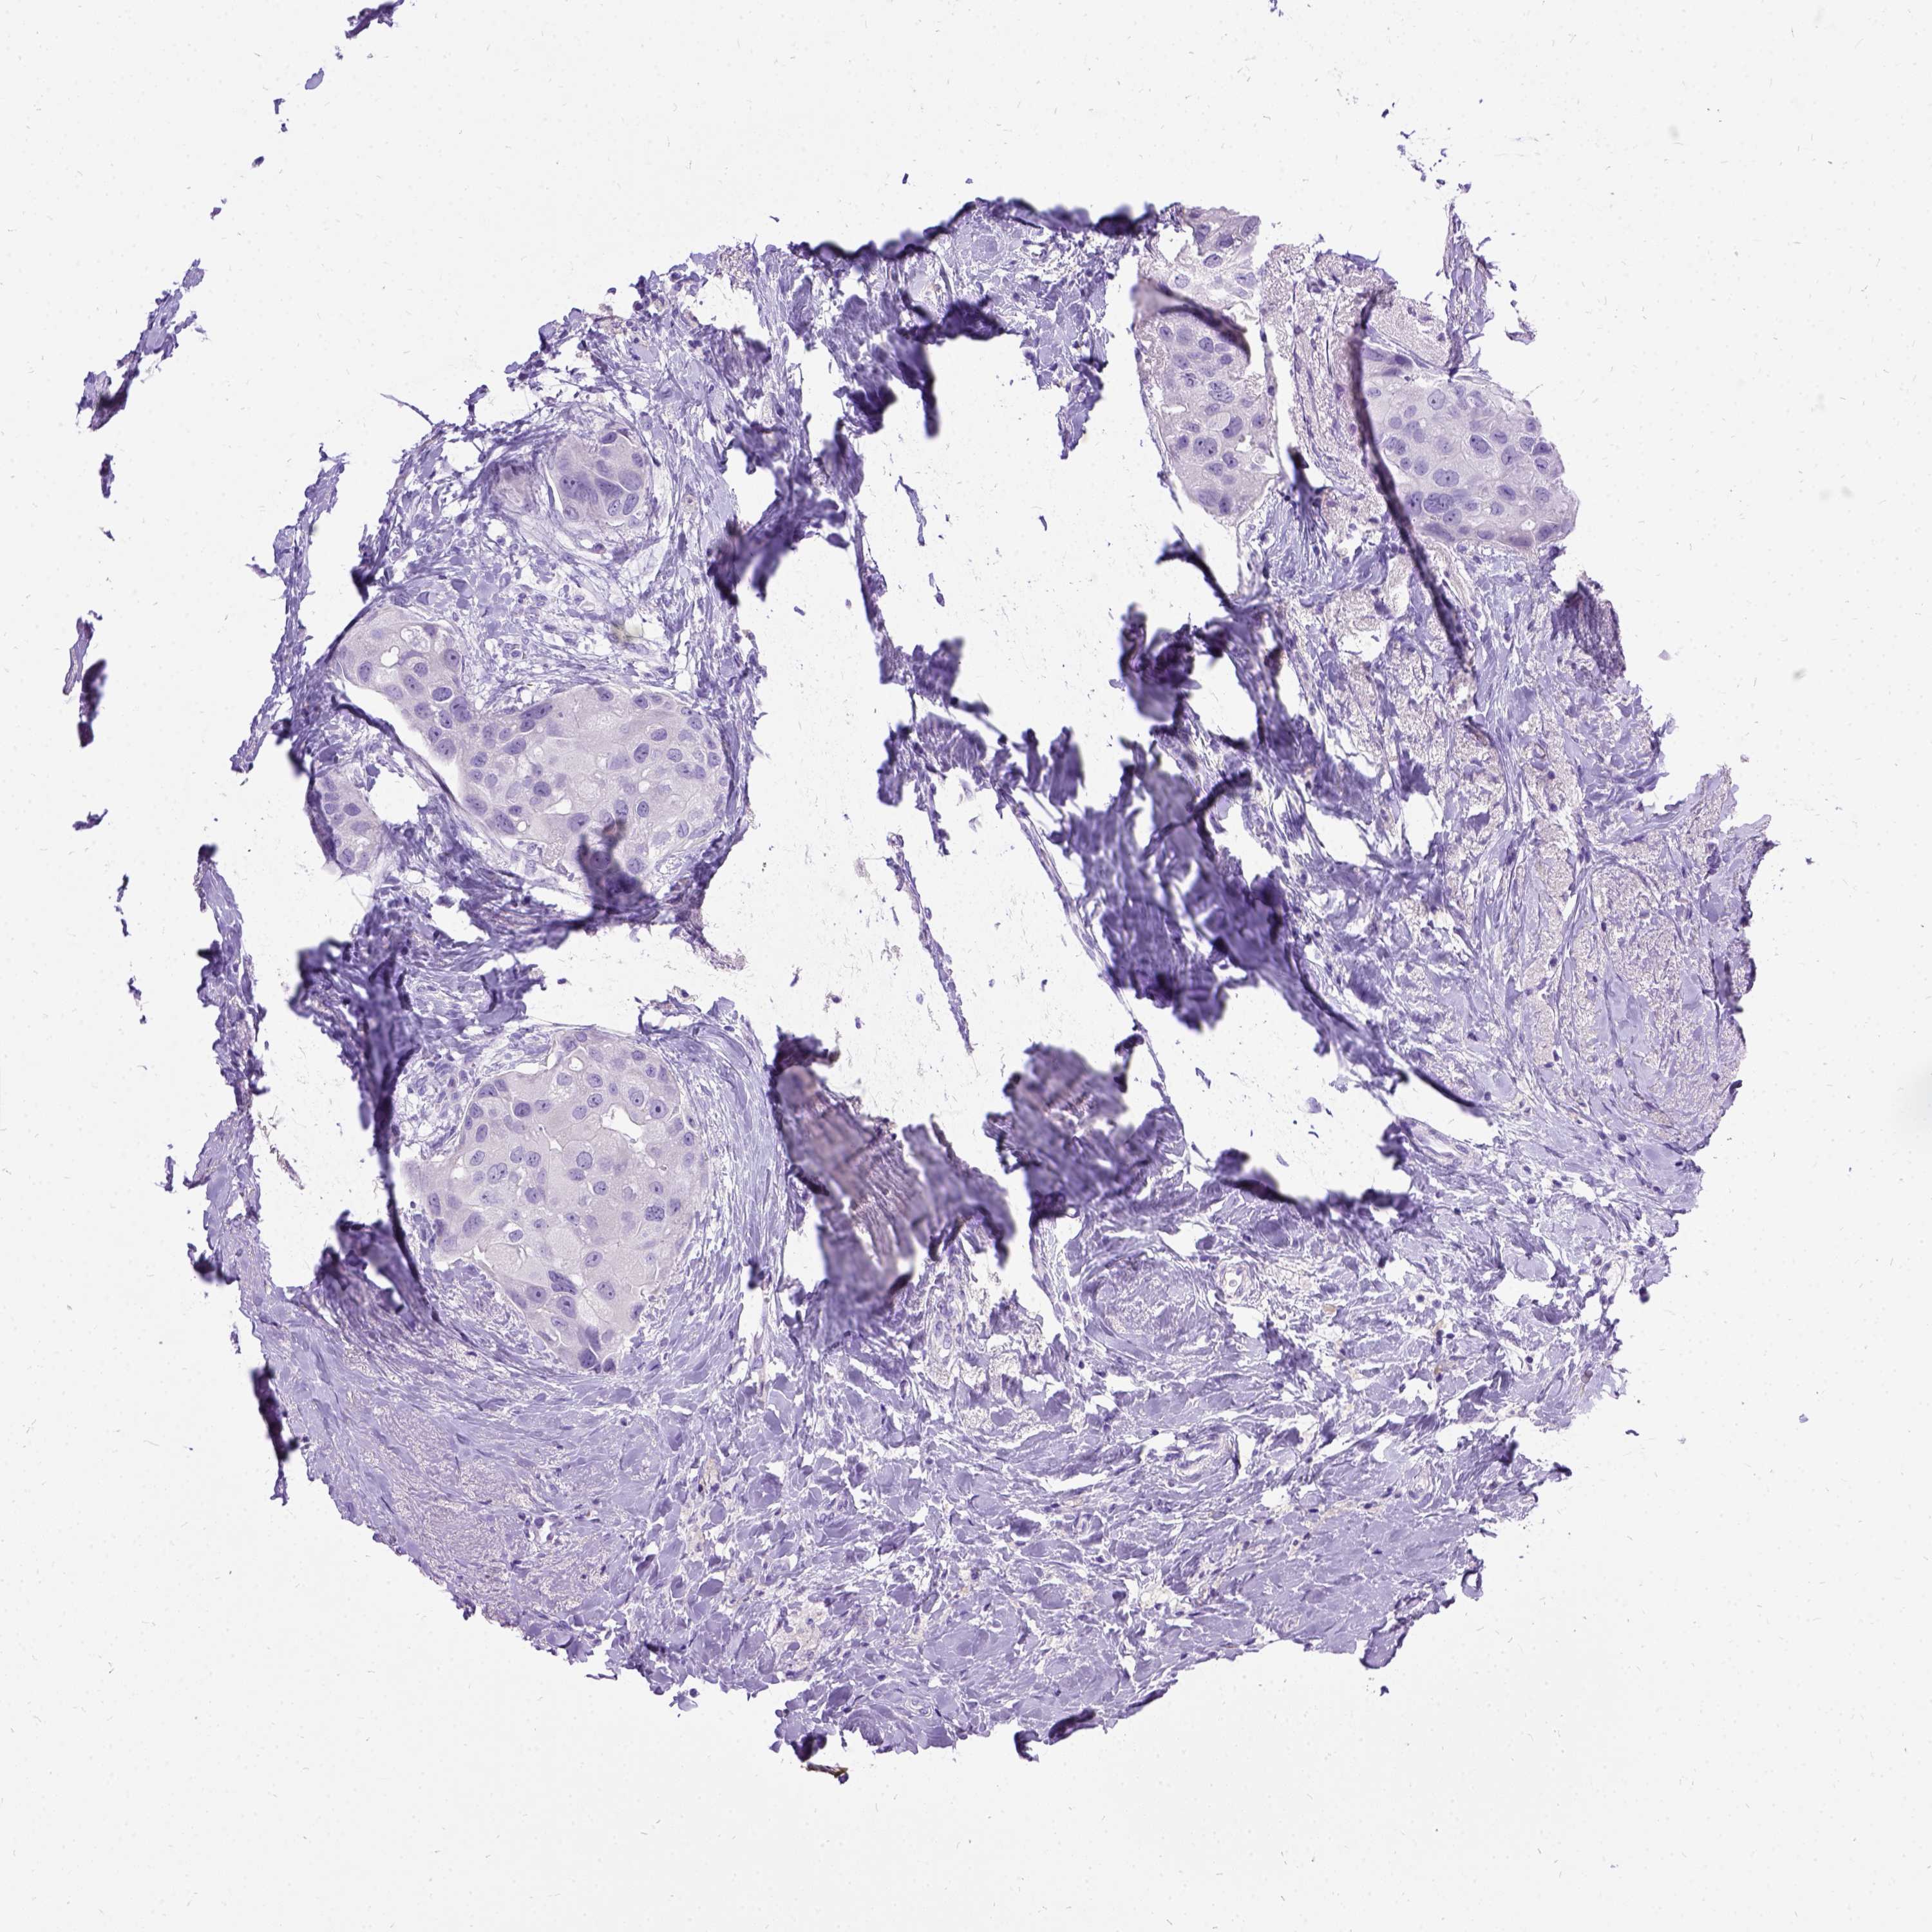

Breast cancer

Human cancer